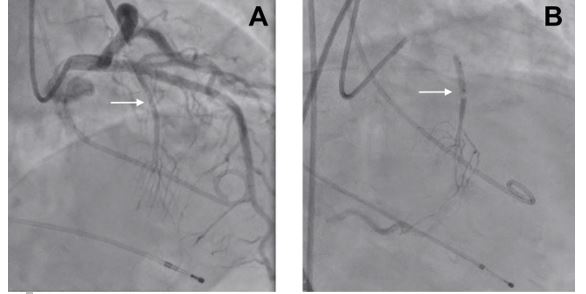

The patient was admitted to the emergency department with acute heart failure with clinical worsening during the last two days. In addition, she presented with cough, expectoration and fever up to 39ºC.  An echocardiogramme on arrival confirmed the known asymmetric hypertrophy of the basal interventricular septum (18 mm), and a severe worsening of the left ventricular outflow tract obstruction (120 mmHg) together with SAM and moderate to severe mitral regurgitation (Figure 1)

Fig 1 CC - Clinical Case - hypertrophic cardiomyopathy.jpg

After a discussion of the case, the heart team decided to implant a transient pacemaker and perform an urgent alcohol septal ablation (ASA). The transient pacemaker was implanted in order to reduce LVOT gradients and in preparation for ASA. ASA relieves LVOTO by creating a localised myocardial infarction in the area of the basal septal muscle where SAM-septal contact is occurring. Following remodelling of this area, the LVOT is widened, thereby relieving LVOT obstruction. Previous clinical cases in the literature have shown a rapid gradient resolution and long-term improvement with ASA.